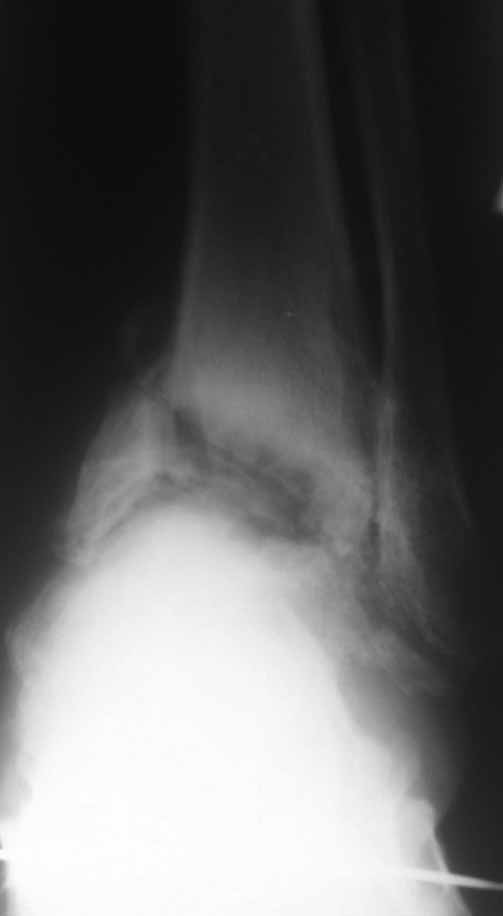

Зачем вытяжение - эффект на рентгенограммах виден.

Склоняемся к мысли, что все таки Charcot's Joint.

Вложение не в текстовом формате было извлечено…

Имя     : На вытяжении 2.jpg

Тип     : image/jpg

Размер  : 29447 байтов

Описание: отсутствует

Url     : http://weborto.net:8080/pipermail/ortho/attachments/20111203/f37772b8/attachment-0005.jpg